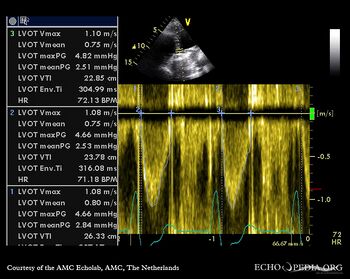

| Continuous-wave Doppler signal of transaortic flow | Pulsed-wave Doppler signal of flow in left ventricle outflow tract |